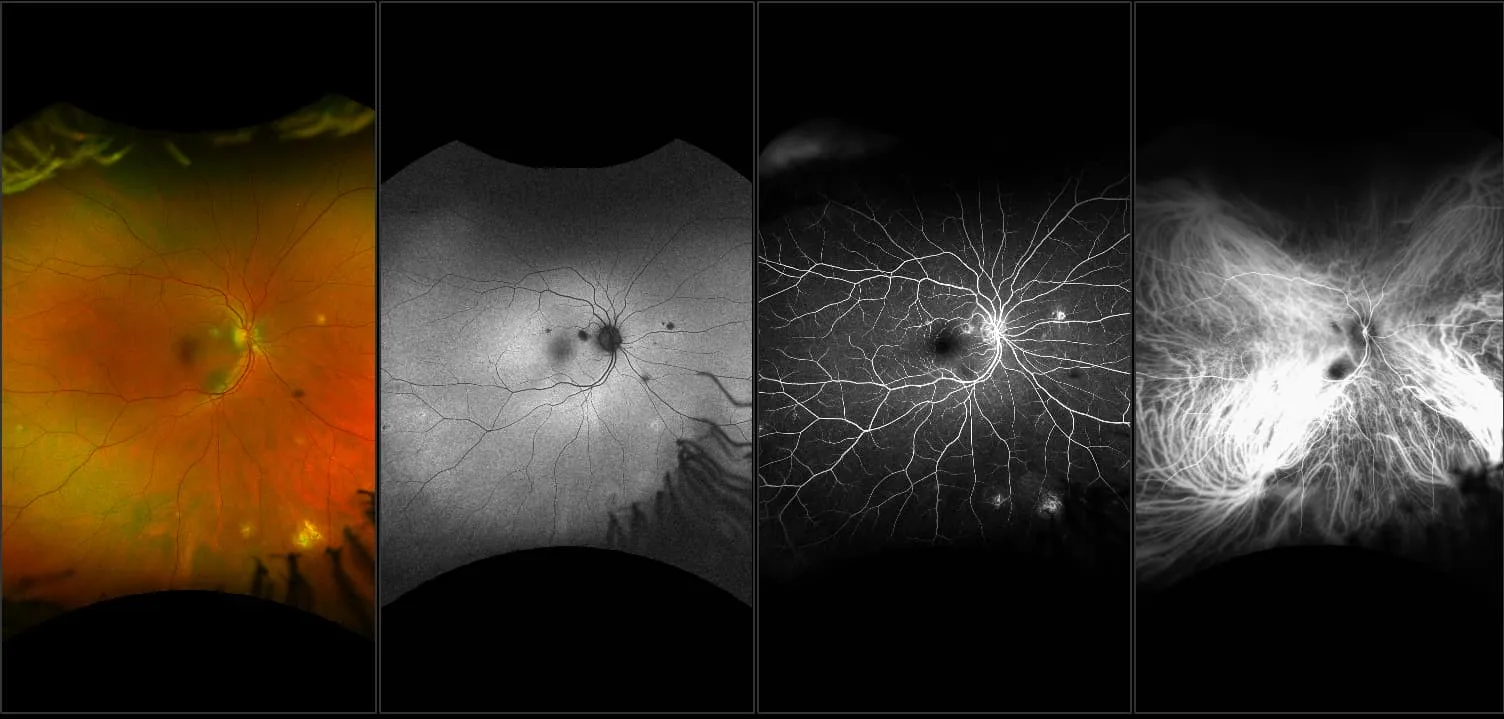

California - Posterior Uveitis with Vitreous Haze, RG, AF

Uveitis is inflammation of the uveal tract which can be caused by autoimmune disorders such as rheumatoid arthritis or infection which can be idiopathic. The uvea is responsible for the transport of blood including inflammatory cells and is critical for vision. It can occur at any age and can result from many causes including systemic disease. Uveitis can be categorized as anterior, intermediate and posterior. Posterior uveitis can cause damage to the optic nerve, abnormally high pressure in the eye, cataracts or an accumulation of fluid within the retina which may cause retinal detachment.